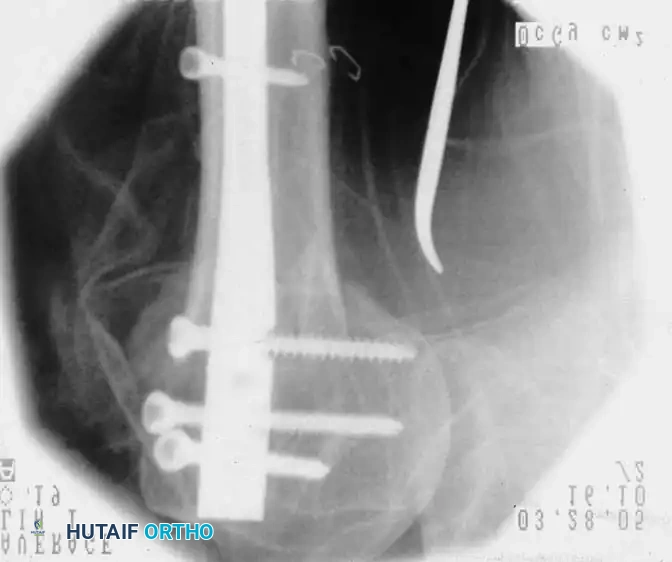

Open Reduction and Internal Fixation (Locked Plating)

For complex three- and four-part fractures, particularly in patients with osteoporotic bone, proximal humeral locking plates have revolutionized treatment. These fixed-angle constructs provide superior biomechanical stability compared to conventional non-locking plates.

Surgical Approach:

* The deltopectoral approach is the workhorse for proximal humeral ORIF, utilizing the internervous plane between the deltoid (axillary nerve) and pectoralis major (medial/lateral pectoral nerves).

* The cephalic vein is identified and typically retracted laterally with the deltoid to protect its tributaries.

Fixation Principles:

* Anatomic reduction of the medial calcar hinge is critical to prevent varus collapse.

* Heavy nonabsorbable sutures are passed through the rotator cuff tendons and tied to the plate to neutralize tuberosity pull.

* Locking screws are placed into the humeral head, ensuring they do not penetrate the articular surface (subchondral placement is ideal).